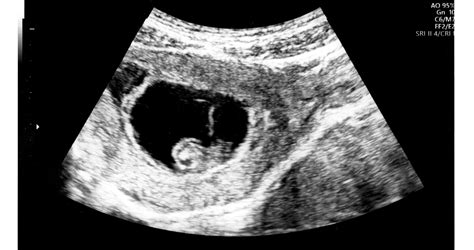

A terhesség 10. hete az embrionális szakasz végét jelenti, innentől kezdve a fejlődő élőlényt már magzatnak nevezzük. Ekkorra a baba egy közel 1 milliárd sejtből álló szervezetté fejlődött, és felnőtt szerveinek több mint 90%-ával rendelkezik. A növekedés rendkívüli ütemben folytatódik tovább.

A tizedik hét az embrionális szakasz vége, ettől a héttől már magzatról beszélünk. Ekkorra a baba egy közel 1 milliárd sejtből álló szervezetté fejlődött, és a felnőtt szerveinek több mint 90%-ával rendelkezik. A növekedés rendkívüli ütemben folytatódik tovább.

A kisbabád homloka ideiglenesen megduzzad a fejlődő agya miatt, és magasan helyezkedik el a fejen, ami itt még a testének felét adja ki. A feje búbjától a faráig csak kicsit több, mint 3 cm hosszú a teste. A 10. héten sok folyadékot nyel és mozgolódik a baba. Ha bekukkanthatnál a méhedbe, olyan apró részleteket pillanthatnál meg, mint például a körmök kialakulása (az úszóhártya már eltűnt!), és a pelyhes haj növekedésének kezdete.

A 10 hetes magzat szíve körülbelül 160-at ver percenként. A 10 hetes magzat méretei: a 10. hétre a magzat ülőmagassága (CRL) 31-39 mm.